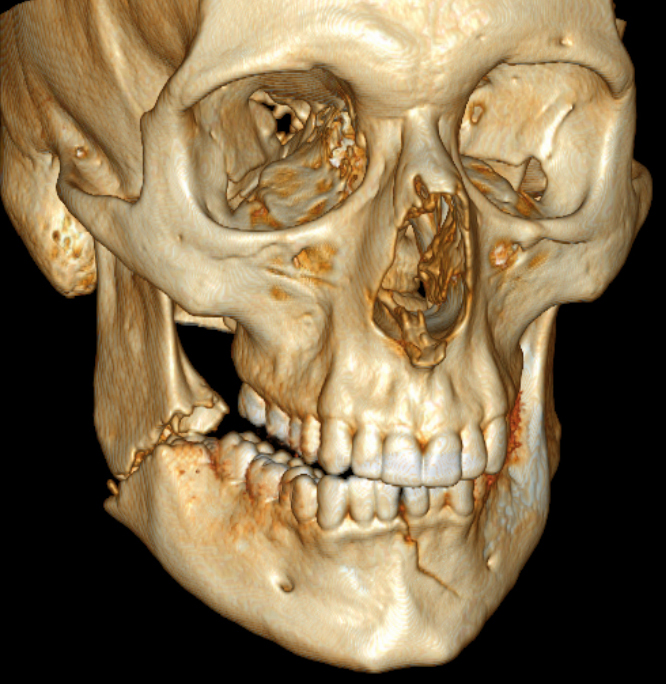

Contributor: Taylor Lynch, MD Educational Pearls: What is orbital compartment syndrome, and how is it assessed in the emergency room? Orbital compartment syndrome (OCS) is an emergent ophthalmic condition in which intraorbital pressure in the orbital compartment rises dramatically, compromising perfusion of the optic nerve and retina, leading to risk of irreversible vision loss. OCS occurs in the context of traumatic lesions with retrobulbar hemorrhage. Intraocular pressures (IOP) are measured via tonometry as a surrogate for intraorbital pressures, with emergent pathology being present when IOP exceeds 30-40 mmHg (normal being around 20 mmHg). What might be some physical exam findings beyond increased IOP for orbital compartment syndrome? Proptosis (physical outward protrusion of eye) with resistance to being pushed posterior. Afferent pupillary defect (when the non-impacted eye has light shown into it, the impacted eye will have pupillary constriction, and when light is removed it will begin to dilate, but when light is shown into the impacted eye, it will not constrict and continue to dilate). Generalized complaints of vision loss or an inability to move the eye. What is the treatment for orbital compartment syndrome? Lateral canthotomy must be performed immediately upon clinical suspicion as permanent vision loss can occur within minutes to hours. Lateral canthotomy Step-by Step: Ideally have the patient sedated or highly cooperative. Numb and vasoconstrict the surrounding eye/orbital skin tissue with lidocaine and epinephrine. Take hemostats and clamp the interior and exterior eyelid at the lateral canthus at a 90º angle towards the orbital rim for 30-60 seconds to further devascularize the region. Take iris scissors and cut laterally to the orbital bone/rim to reveal the lateral lanthal tendon. Cut the inferior crus of the lateral lanthal tendon as this will provide the most significant reduction in IOP. Reassess IOP during each step of the procedure to measure procedure efficacy. If no pressure reduction is noted with inferior cantholysis, cutting the superior crus of the lateral canthal tendon may be required to further allow the eye to bulge out and reduce intraorbital pressure. Big takeaways? Ocular compartment syndrome is a rare but emergent vision threatening condition that requires immediate lateral canthotomy to reduce intraocular and intraorbital pressures. Lateral canthotomy done within 30-60 minutes of symptom development can save the patient from permanent vision loss. References: Mohammadi F, Rashan A, Psaltis A, et al. Intraocular Pressure Changes in Emergent Surgical Decompression of Orbital Compartment Syndrome. JAMA Otolaryngol Head Neck Surg. 2015;141(6):562-565. doi:10.1001/jamaoto.2015.0524 Haubner F, Jägle H, Nunes DP, et al. Orbital compartment: effects of emergent canthotomy and cantholysis. Eur Arch Otorhinolaryngol. 2015;272(2):479-483. doi:10.1007/s00405-014-3238-5 Bailey LA, van Brummen AJ, Ghergherehchi LM, Chuang AZ, Richani K, Phillips ME. Visual Outcomes of Patients With Retrobulbar Hemorrhage Undergoing Lateral Canthotomy and Cantholysis. Ophthalmic Plast Reconstr Surg. 2019;35(6):586-589. doi:10.1097/IOP.0000000000001401 Summarized by Dan Orbidan, OMS2 | Edited by Dan Orbidan and Jorge Chalit, OMS4 Donate: https://emergencymedicalminute.org/donate/